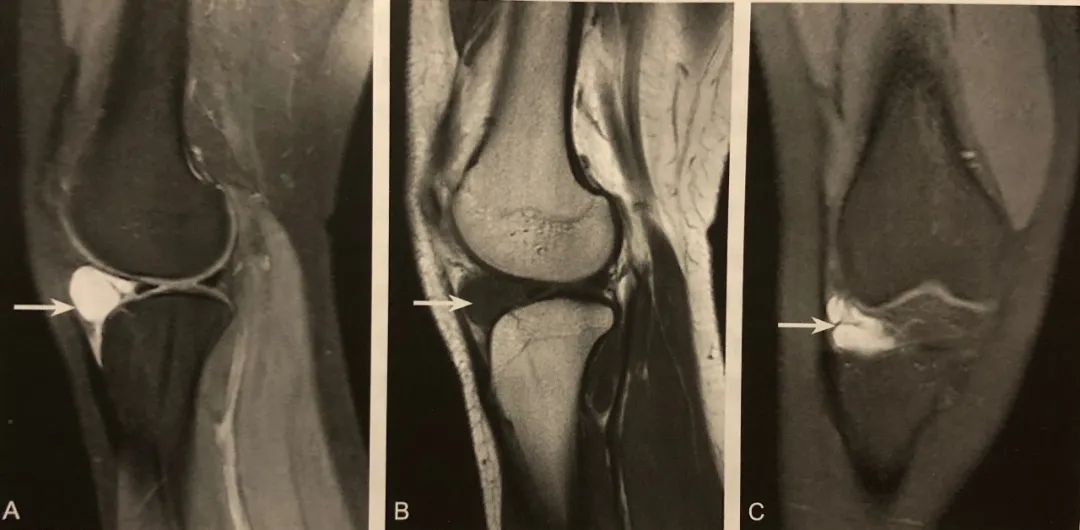

1. 腓骨小头撕脱性骨折的直接征象,弓形复合体和后外侧角损伤的间接征象;

2. 在膝关节X线前后位或 CT、MRI 冠状位观察,表现为近端腓骨小头或腓骨茎突撕脱性骨折,碎骨片呈弓形;

3. X 线片或 CT 观察到弓形征后,须行 MRI 检查,观察弓形复合体及后外侧角的完整性;

4. 少数后外侧角损伤合并腓总神经及胭动静脉损伤。